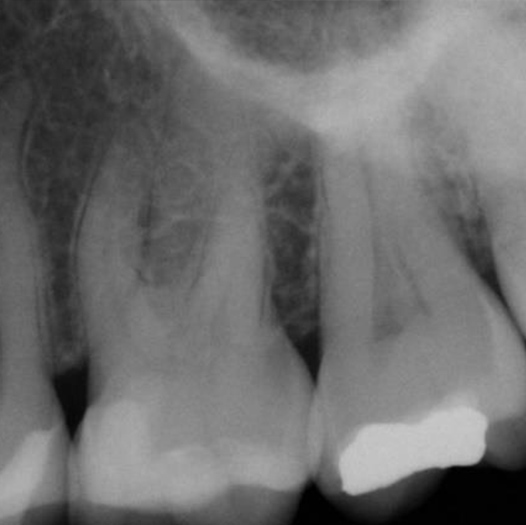

Before

Before Root Canal treatment